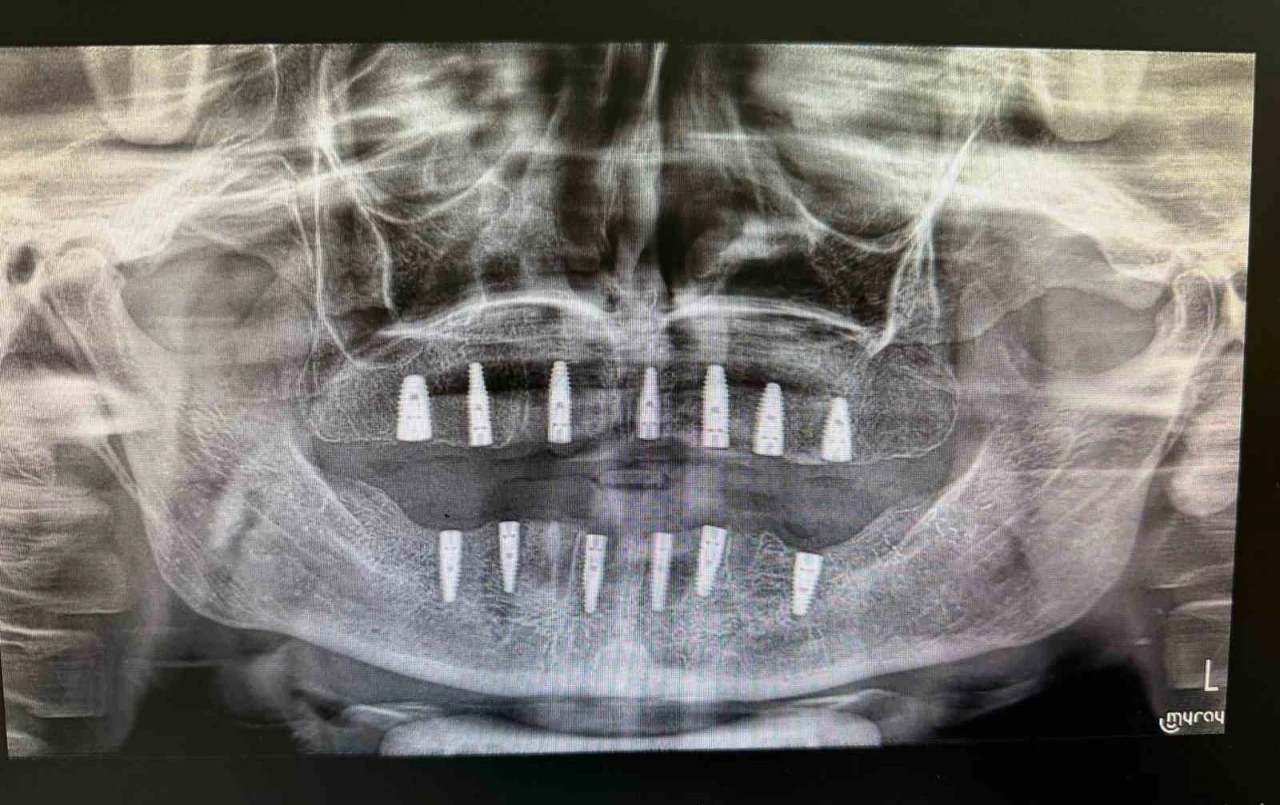

Bayburt Ağız ve Diş Sağlığı Merkezinde tamamen dişleri olmayan bir hastaya implant tedavisi uygulandı. Tedavi sonrası hasta, yeni dişlerine kavuştu.

Merkezde görevli Uzm. Dt. Sefa Merve Arıkan tarafından gerçekleştirilen ameliyatta hastaya 13 adet implant yerleştirildi.

Diş implantı, çene kemiğine yerleştirilen ve eksik dişlerin işlevini üstlenen yapay diş kökleri olarak biliniyor. Genellikle dişini kaybetmiş veya hiç dişi bulunmayan hastalara uygulanan bu yöntem, hem estetik görünüm hem de çiğneme fonksiyonunun yeniden kazanılmasını sağlıyor.

Tedavinin ardından hastanın, iyileşme süreci tamamlandığında normal beslenme ve konuşma yetilerini rahatlıkla kullanabileceği öğrenildi.